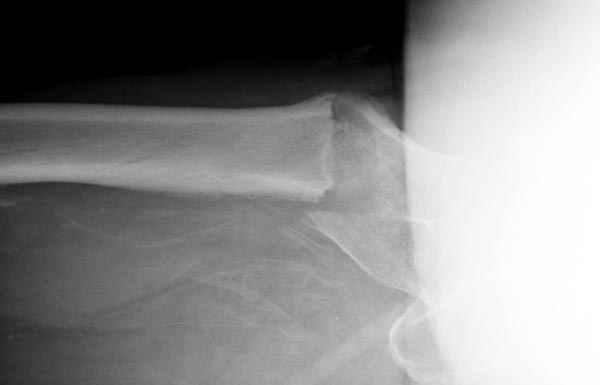

Зона раскола во время моей ревизии проходит по боковой поверхности как раз в зоне введения шеечного винта (картина как топор разрубил полено на две равных части, можа сделать КТ?)

Зона введения и вообще латеральная стенка тут не имеет значения, поскольку угловая стабильность обеспечивается самим фиксатором.

В общем, сделали. См. приложение.

Длина и из-за этого ось получились не совсем такие, как хотелось бы, все-таки срок после той операции уже 6 недель. Может быть, стоило провести дистракцию аппаратом неделю-другую. Заранее спасибо за комментарии и критику.